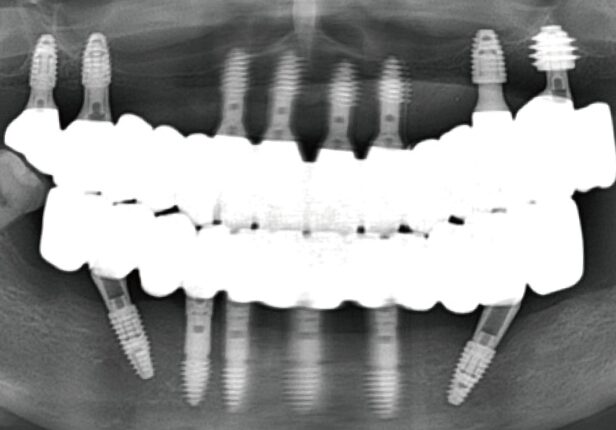

Panorâmica Pós-Cirúrgia

caso de estudo